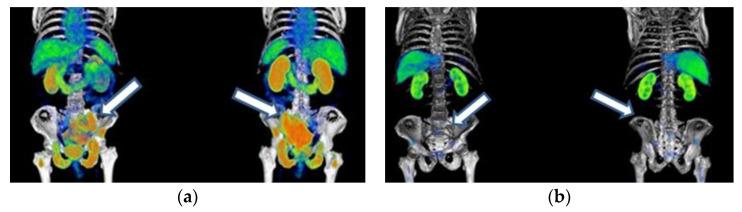

Lu-iPSMA is a novel radioligand developed at ININ-Mexico with a high affinity for the PSMA protein heavily expressed in cancer cells of approximately 95% of patients with metastatic castration-resistant prostate cancer (mCRPC). Lu-DOTATOC is a patent-free radioligand, molecularly recognized by somatostatin receptors (SSTR-2) overexpressed in cancer cells of about 80% of patients with metastatic gastroenteropancreatic neuroendocrine tumors (GEP-NET). This translational research aimed to determine the efficacy and safety of Lu-iPSMA and Lu-DOTATOC developed as GMP pharmaceutical formulations for treating progressive and advanced mCRPC and NET. One hundred and forty-five patients with mCRPC and one hundred and eighty-seven subjects with progressive NET (83% GEP-NET and 17% other NET), treated with Lu-iPSMA and Lu-DOTATOC, respectively, were evaluated. Patients received a mean dose of 7.4 GBq per administration of Lu-iPSMA (range 1-5 administrations; 394 treatment doses) or Lu-DOTATOC (range 2-8 administrations; 511 treatment doses) at intervals of 1.5-2.5 months. Efficacy was assessed by SPECT/CT or PET/CT. Results were stratified by primary tumor origin and number of doses administered. Patients with mCRPC showed overall survival (OS) of 21.7 months with decreased radiotracer tumor uptake (SUV) and PSA level in 80% and 73% of patients, respectively. In addition, a significant reduction in pain (numerical scale from 10-7 to 3-1) was observed in 88% of patients with bone metastases between one and two weeks after the second injection. In the GEP-NET population, the median progression-free survival was 34.7 months, with an OS of >44.2 months. The treatments were well tolerated. Only ten patients experienced grade ≥ 3 myelosuppression (3% of all patients). The observed safety profiles and favorable therapeutic responses demonstrated the potential of Lu-iPSMA and Lu-DOTATOC to improve overall survival and quality of life in patients with progressive and advanced mCRPC and NET.

镥-PSMA是墨西哥国立核科学研究所研发的一种新型放射性配体,对约95%的转移性去势抵抗性前列腺癌(mCRPC)患者癌细胞中高表达的PSMA蛋白具有高亲和力。镥-奥曲肽是一种无专利的放射性配体,可被约80%的转移性胃肠胰神经内分泌肿瘤(GEP-NET)患者癌细胞中过表达的生长抑素受体(SSTR-2)分子识别。这项转化研究旨在确定作为药品生产质量管理规范(GMP)制剂开发的镥-PSMA和镥-奥曲肽治疗进展期和晚期mCRPC及神经内分泌肿瘤(NET)的疗效和安全性。分别对145例mCRPC患者和187例进展期NET患者(83%为GEP-NET,17%为其他NET)进行了评估,这些患者分别接受了镥-PSMA和镥-奥曲肽治疗。患者接受镥-PSMA(范围为1至5次给药;394个治疗剂量)或镥-奥曲肽(范围为2至8次给药;511个治疗剂量),每次给药平均剂量为7.4GBq,给药间隔为1.5至2.5个月。通过单光子发射计算机断层扫描/计算机断层扫描(SPECT/CT)或正电子发射断层扫描/计算机断层扫描(PET/CT)评估疗效。结果按原发肿瘤来源和给药剂量数进行分层。mCRPC患者的总生存期(OS)为21.7个月,分别有80%和73%的患者放射性示踪剂肿瘤摄取(SUV)和前列腺特异抗原(PSA)水平降低。此外,在第二次注射后1至2周内,88%的骨转移患者疼痛显著减轻(数字评分从10 - 7降至3 - 1)。在GEP-NET人群中,无进展生存期的中位数为34.7个月,总生存期>44.2个月。这些治疗耐受性良好。只有10例患者出现≥3级骨髓抑制(占所有患者的3%)。观察到的安全性概况和良好的治疗反应表明,镥-PSMA和镥-奥曲肽有潜力改善进展期和晚期mCRPC及NET患者的总生存期和生活质量。